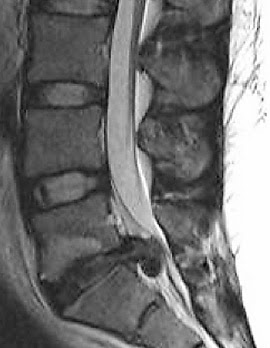

Laminectomy is the surgery

which removes a portion of the vertebral bone called as lamina. Lamina Lies

between the spinous process it is a posterior arch of the vertebral bone.

There is also a secondary

process which is called as laminotomy which is generally used for the removal

of mid portion of selected one lamina

with conventional technique.